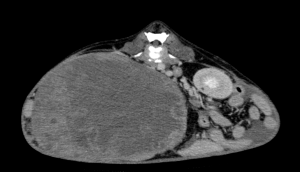

今回治療させていただいたワンちゃんは、ここ1年ほどでお腹が張ってきており、散歩中に立てなくなったとの事で来院されました。原因は、巨大な脾臓腫瘍と、脾臓腫瘍から壊死物質が漏れたことによる腹膜炎でした。重度の貧血を呈していたため、輸血で状態を安定化し、翌日に手術を行いました。脾臓腫瘍は、直径20センチ、重さ2.7kgで、病理組織学的検査は「脂肪肉腫」でした。幸いなことに、手術前のCT検査で転移所見はありませんでした。